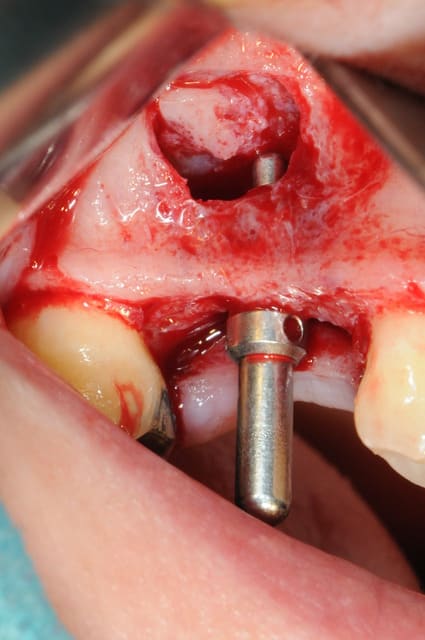

les premières photos, c'était ouverture par voie latérale

les suivantes;

- forage et transperçage de la crête sans aller trop loin...

- essayage pilier pour parallélisme

- forage à 3mm

- visualisation de la hauteur sous la membrane de Schneider

- utilisation d'un ostéotome diamètre 3.4 puis 3.8

(sous dimensionnement de diamètre par rapport à l'implant prévu :4mm)

- mise en place de l'implant

- séchage discret de la surface osseuse

- injection du Vital Os en palatin et partout autour de l'implant

- hé hé hé ... pas de membrane de recouvrement, le matériaux se suffit à lui même. d'où une petite économie substantielle pour ceux qui ont l'habitude de mettre systématiquement une membrane après un Caldwell-Luc.

- sutures...